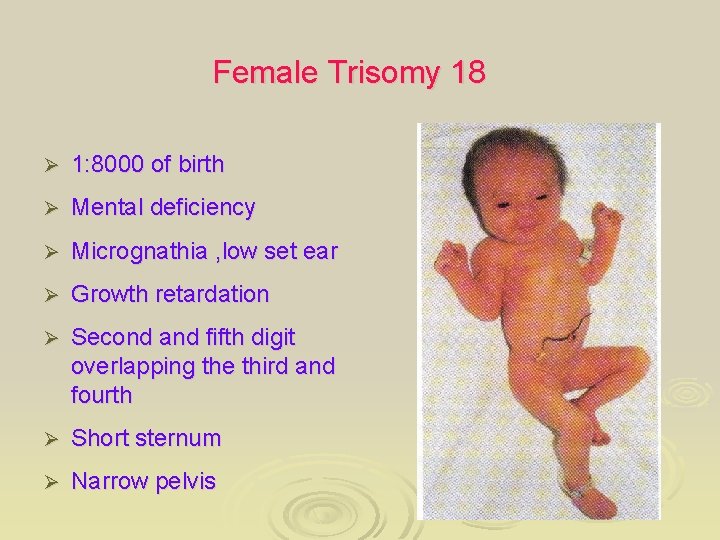

Female Trisomy 18 Ø 1: 8000 of birth Ø Mental deficiency Ø Micrognathia , low set ear Ø Growth retardation Ø Second and fifth digit overlapping the third and fourth Ø Short sternum Ø Narrow pelvis